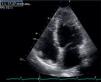

The transthoracic echocardiogram revealed apical LV hypertrophy with a typical spade-like geometry of the LV cavity at end-diastole (LV wall thickness 17 mm) (Figure 2) and LV diastolic dysfunction (impaired relaxation) (Figure 3) with normal ejection fraction. No structural or functional valve disease was present.